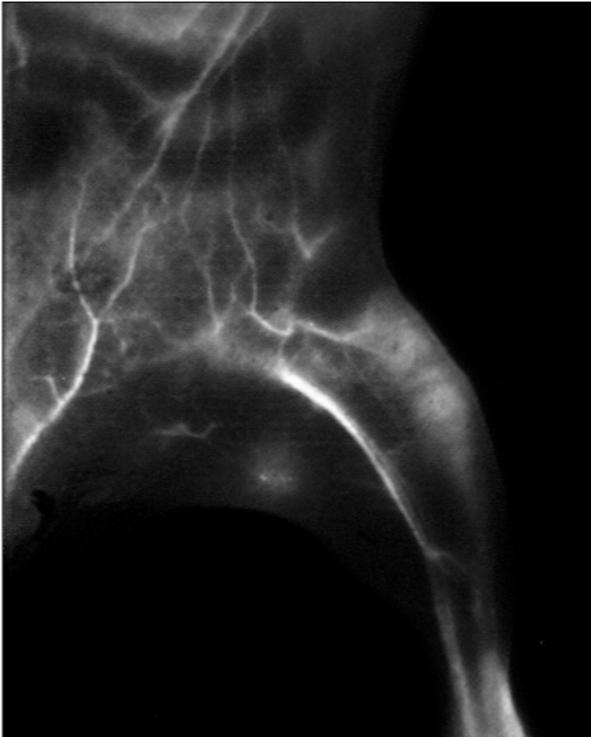

According to a recent report, artificial neural networks can improve the signal-to-background ratio in near-infrared imaging (NIR), sharpening blurred images into high resolution clinical pictures. The NIR-IIb probes that produce the deepest tissue penetration and sharpest images often have toxic elements, making them unfeasible for use in medical imaging for humans. Zhuoran Ma and colleagues investigated a way to improve the image contrast and clarity of FDA-approved biocompatible dyes, which typically detect fluorescence in the 700-1,000 nm range of the near infrared spectrum. Using approximately 2,800 in vivo images taken in mice, the authors trained, validated, and tested artificial neural networks with the intent to transform images produced in the shorter wavelengths into ones that resemble images taken in the NIR-IIb window of 1,500-1,700 nm. In a mouse injected with an FDA-approved dye, the neural network increased the signal-to-background ratio of lymph node images taken to greater than 100. The authors also compared the deep learning-enhanced imaging to actual NIR-IIb imaging of a mouse tumor. The enhanced image showed a 26.2 tumor-to-normal tissue signal ratio vs the actual image's 30.8. According to the authors, deep learning assisted imaging could improve diagnostics and image-guided surgery in the clinic.

Article #20-21446: "Deep learning for in vivo near-infrared imaging," by Zhuoran Ma, Feifei Wang, Weizhi Wang, Yeteng Zhong, and Hongjie Dai.